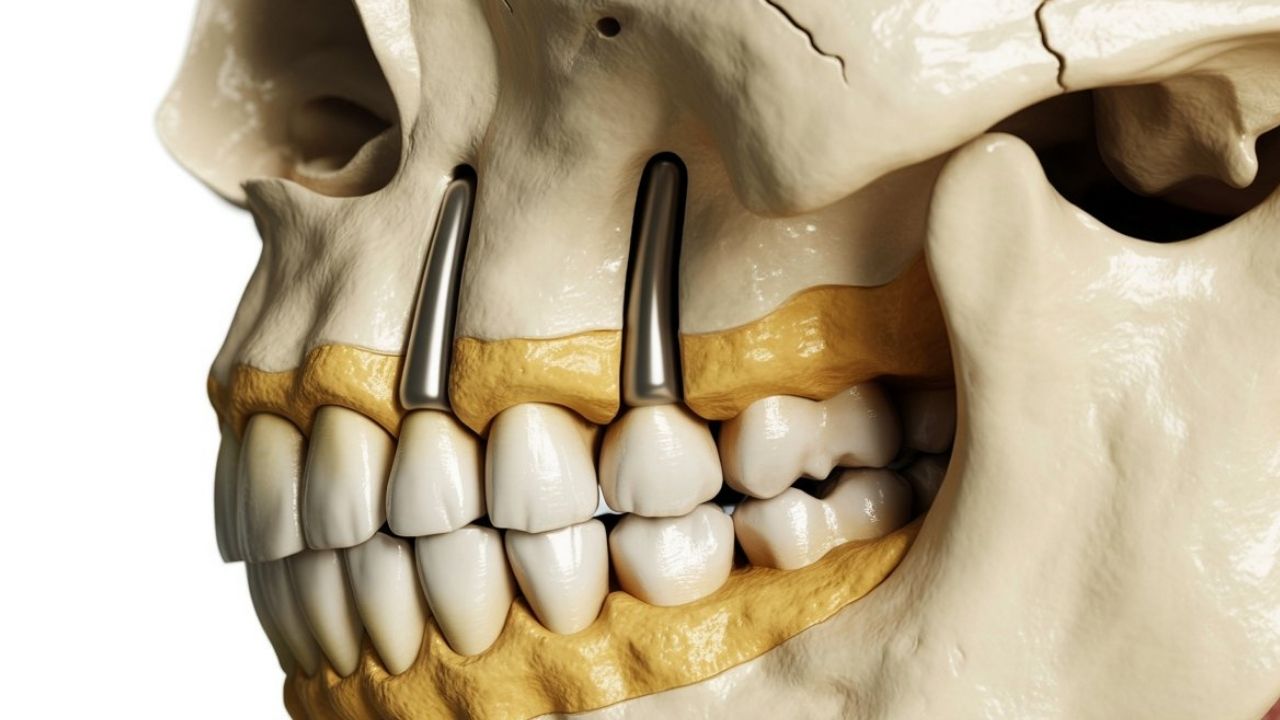

Traditional implants are placed into the jawbone and are ideal when you have adequate bone volume and density. When the upper jaw has resorbed (shrunk) substantially, conventional implants may first require sinus lifts or bone grafting, adding cost and time. Zygomatic implants are longer implants that engage the zygomatic bone (cheekbone)—a denser anchor—so clinicians can restore the upper arch even when the maxillary bone is too thin or soft for standard implants without major augmentation.

Zygomatic fixtures are longer and often require custom or premium components and multi-unit abutments engineered for full-arch alignment. These devices cost more than typical endosteal implants.